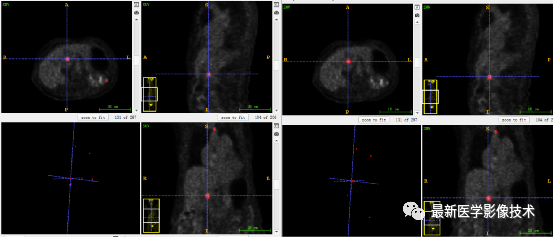

7、验证集分割结果:输入整个图像通过滑窗叠加预测结果,左图是金标准,右图是预测结果